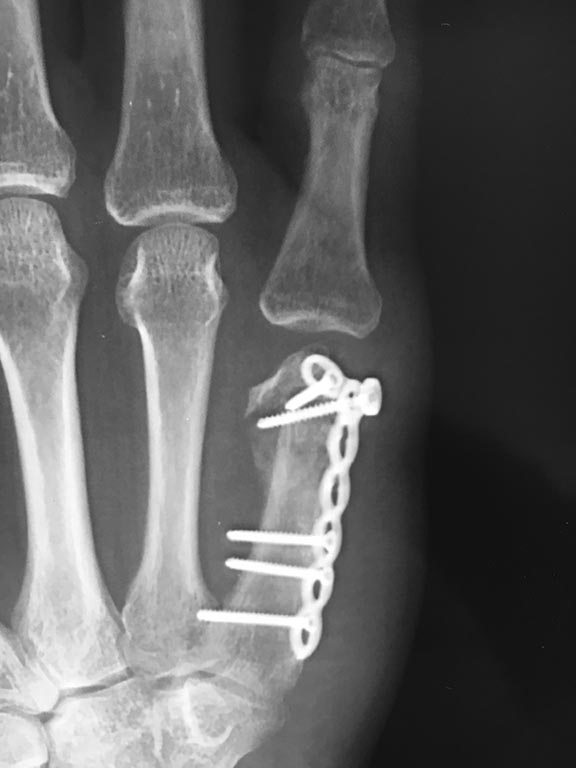

Пациент 41 года, трудоспособный, обратился через 2 недели после

полученной травмы.(механизм травмы скрывает. но скорее всего дал кому-то

в глаз), иммобилизации не выполнялась, т.к. не обращался.

На первичных снимках - головка смещена практически на 90* (к

сожалению не сохранился). Прооперирован, на операции- головка

раздроблена, множество мелких осколков, более крупные практически 60%

лизированы. Головку собрали из "чего Бог пошлет", фиксировали Т образной

пластиной Syhthes 2,0.

Подскажите, пожалуйста, что дальше?

1. Попытаться разработать что осталось от сустава (в клинике есть свой

реабилитационной центр)

2. Направить на эндопротезирование

3.Ваши мнения